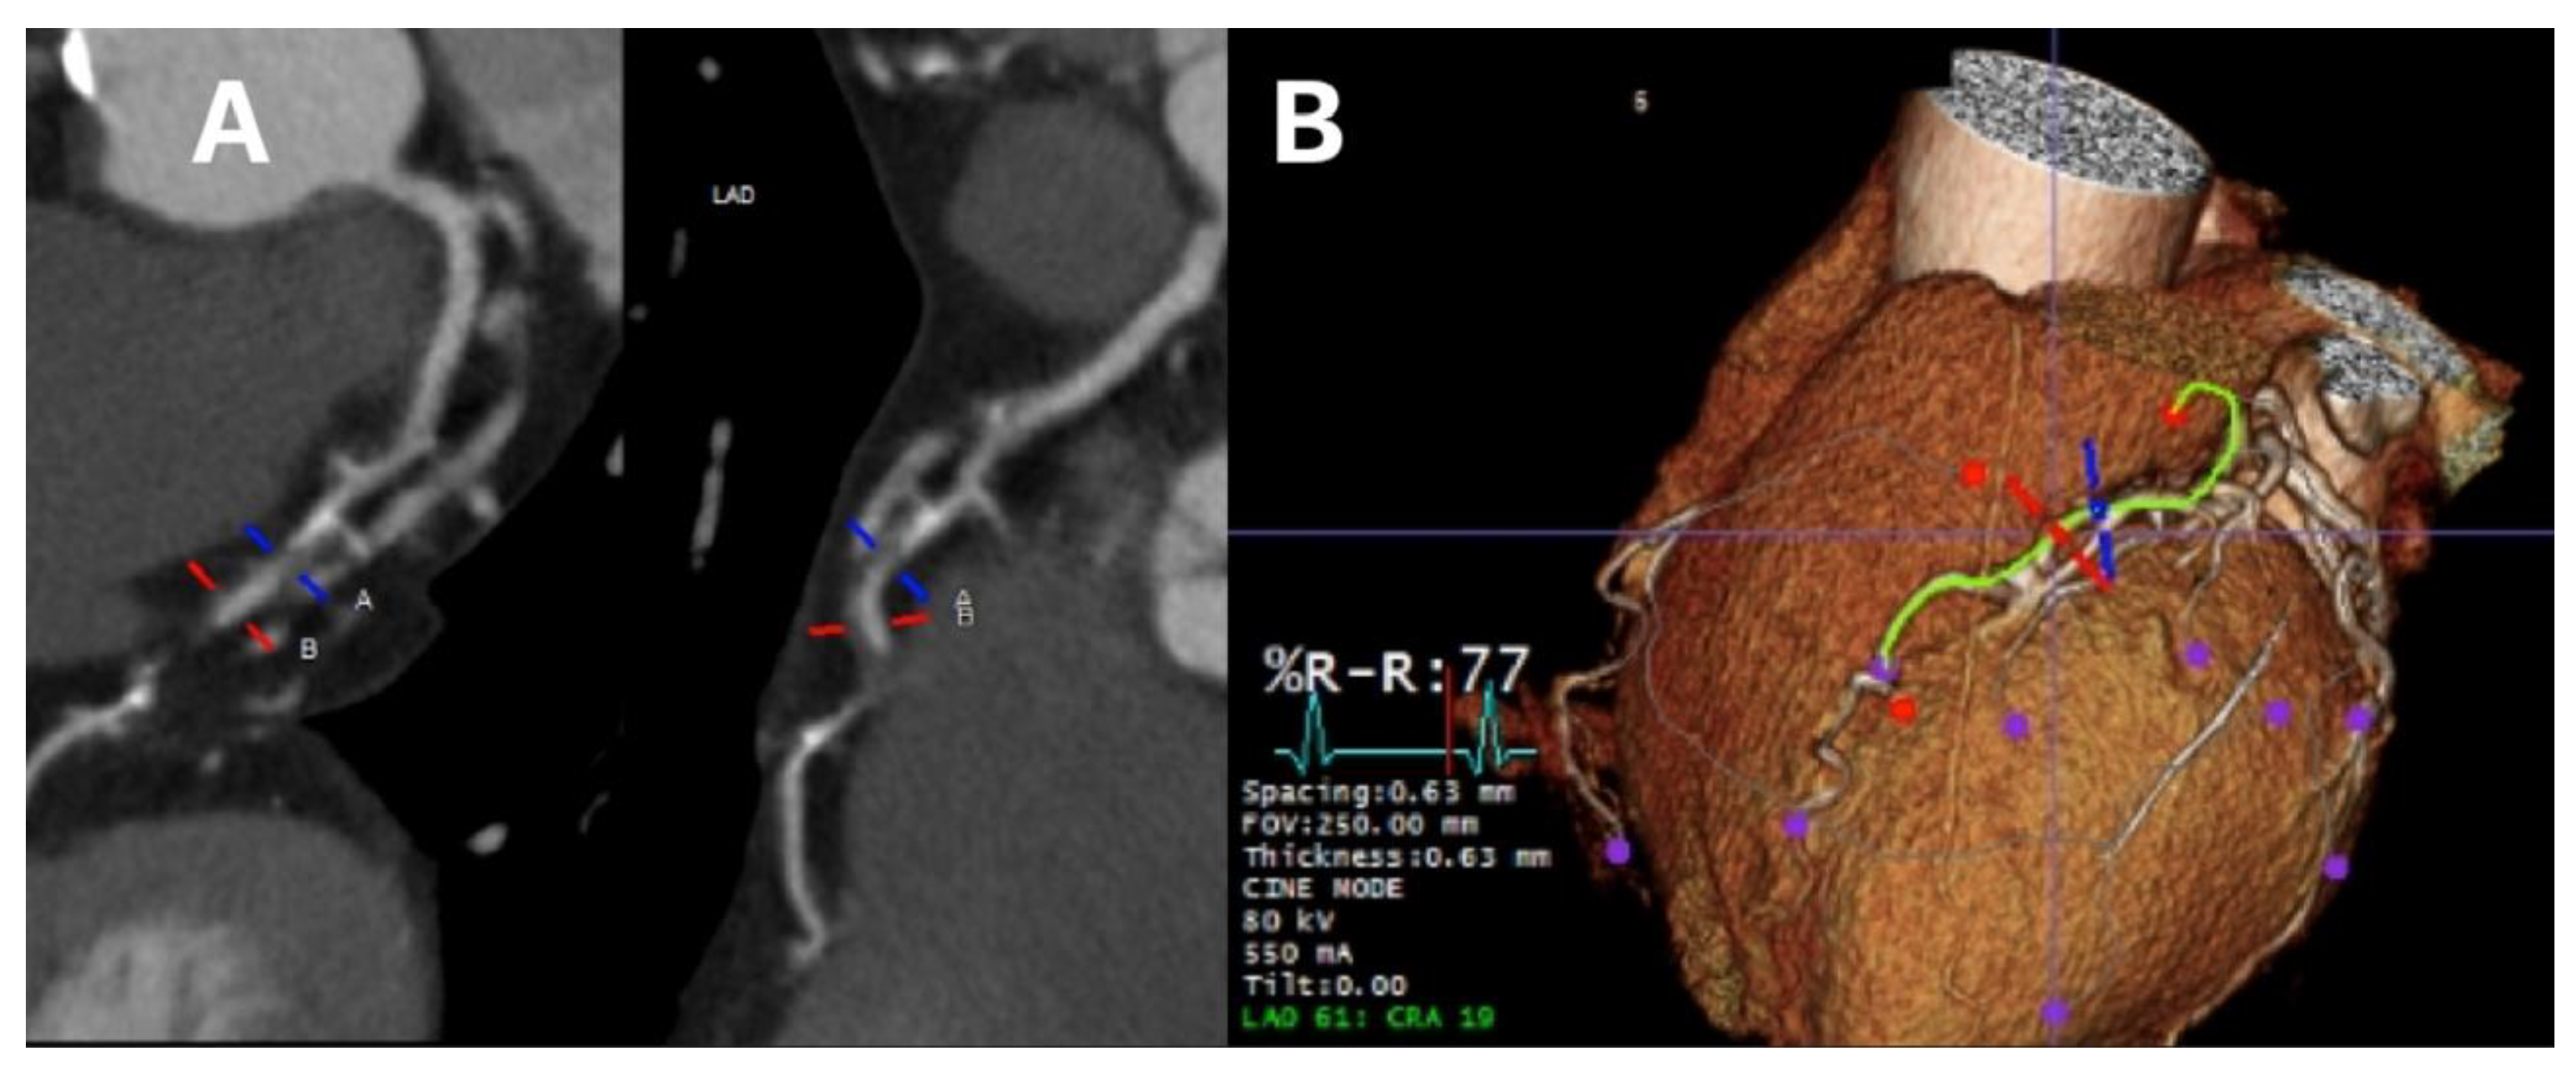

In regards to luminal assessment, CTCA aids in providing optimal images for angiographic projection in the catheter lab thereby minimizing vessel foreshortening, which is of particular benefit in evaluation of lesions which bifurcate [22]. Analysis of the coronary arteries using CT has been shown to have a high concordance with true luminal dimensions when compared to invasive angiography. This can help to define both lesion severity during assessment and selection of stent size in percutaneous revascularisation planning [23]. Further, technological developments in recent years have advanced diagnostic performance of CTCA in detecting significant coronary artery stenosis (>50% luminal narrowing) even in patients with high heart rate and atrial fibrillation [24]. Figure 2 shows luminal assessment of a gated-CTCA demonstrating a severe stenosis in the proximal LAD on the vessel image (panel A) and the 3D reconstruction (panel B).

Figure 2. Luminal assessment from gated CTCA. Panel A shows the lumen of the LAD, with severe mid-proximal stenosis. Panel B shows the 3D reconstruction of the same artery.